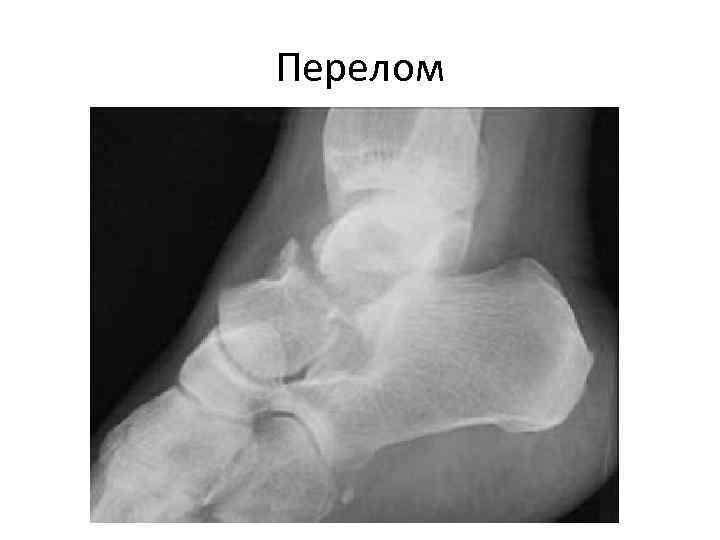

Перелом

Рентгенография стопы в 3 -х проекциях. Перелом таранной кости